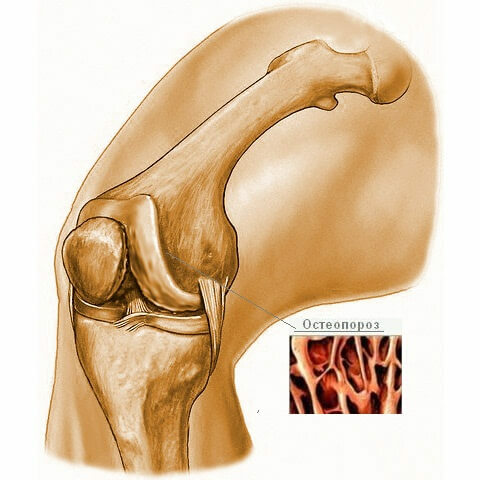

Рисунки Суставов: Анатомические Иллюстрации